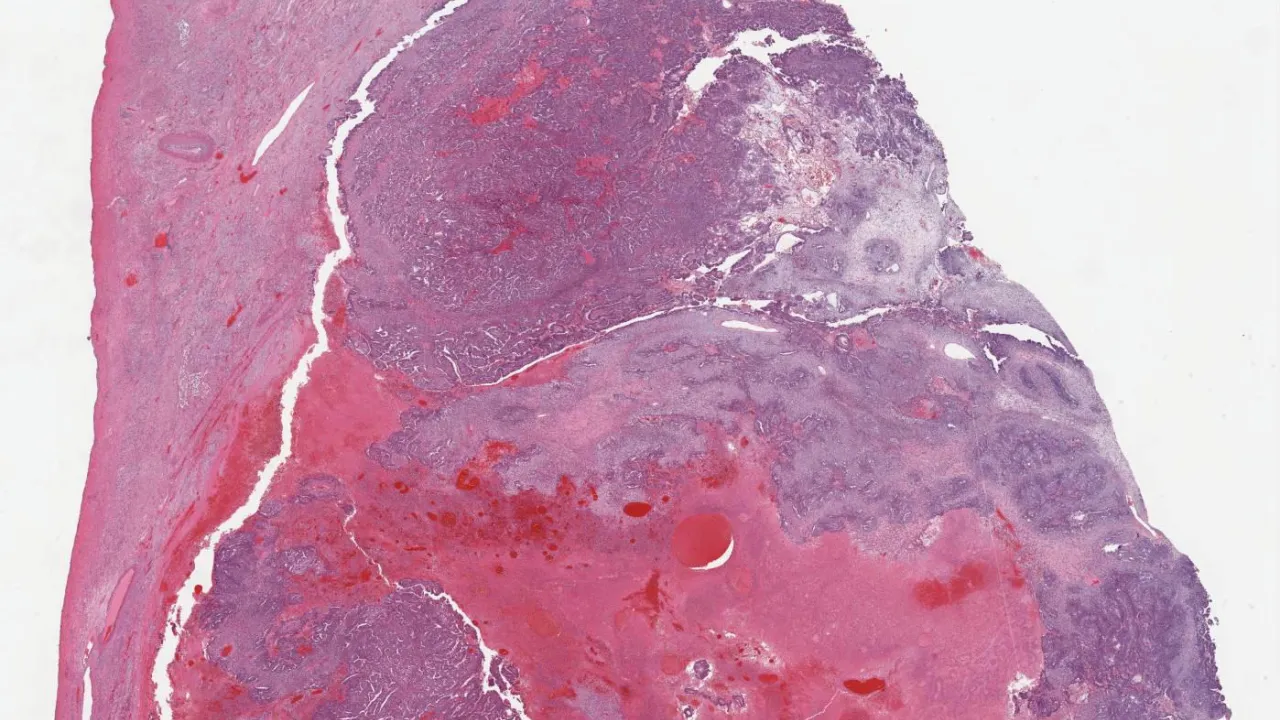

Soft Tissue, Kaposiform hemangioendothelioma